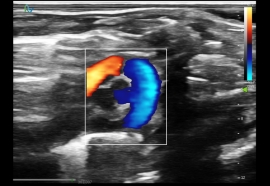

高频超声成像